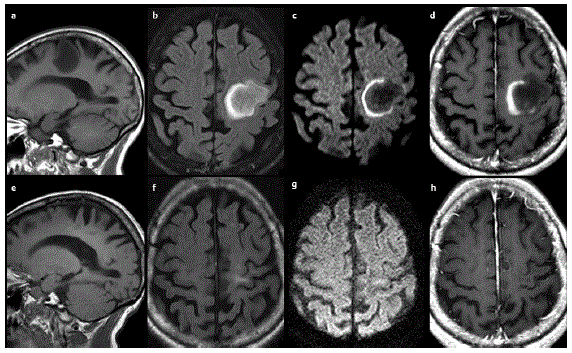

CASO 1. Mulher de 40 anos deu entrada em urgência devido a crises convulsivas e déficit motor. Durante acompanhamento médico, teve as seguintes imagens no diagnóstico e 1 ano após diagnóstico, sem ter sido submetida a qualquer tratamento específico.

a: sagital T1; b: axial t2 flair; c: axial difusão; d: axial T1 contrastada. e, f, g, h: são as imagens correspondentes às superiores 1 ano após.